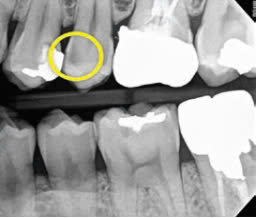

Hình 1: Hình ảnh định lượng ánh sáng huỳnh quang (ánh sáng trắng và ánh sáng huỳnh quang) ở lỗ sâu phía gần bằng thiết bị Qraypen và phim cánh cắn.